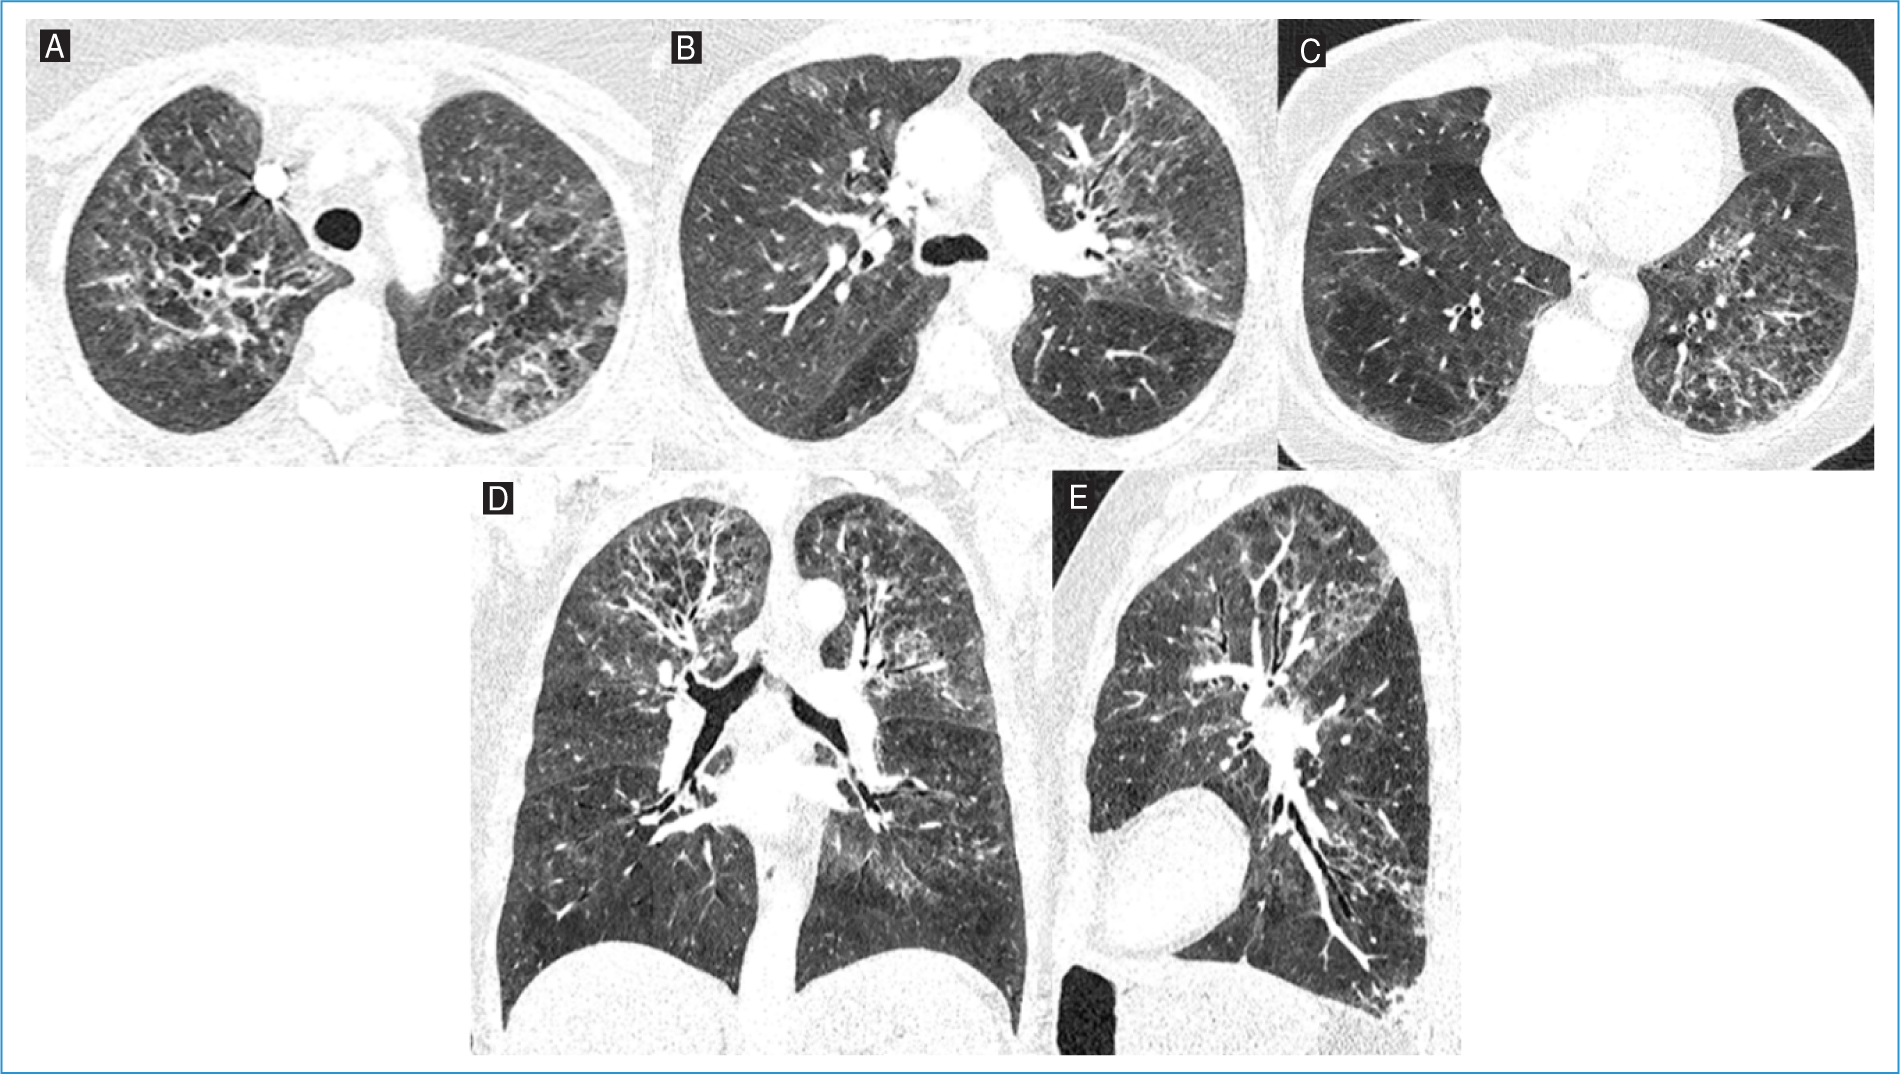

During hospital stay, there was worsening hypoxemia with increasing oxygen support and admission to the ICU. Thoracic CT angiography excluded pulmonary embolism and documented extensive pulmonary parenchymal involvement with ground-glass opacities and consolidations, sparing only a few areas in the upper lung lobes (Fig. 2). Tests for respiratory viruses (such as SARS-CoV-2, influenza A/B, and respiratory syncytial virus) and Legionella pneumophila and Streptococcus pneumoniae antigens were negative.

Figure 2. Axial lung window images of the A: upper, B: middle, and C: lower lobes, along with D: coronal and E: sagittal reconstructions from thoracic computed tomography angiography of Patient #2. Extensive pulmonary parenchymal involvement with ground-glass opacities and consolidations, sparing only a few areas in the upper lung lobes.